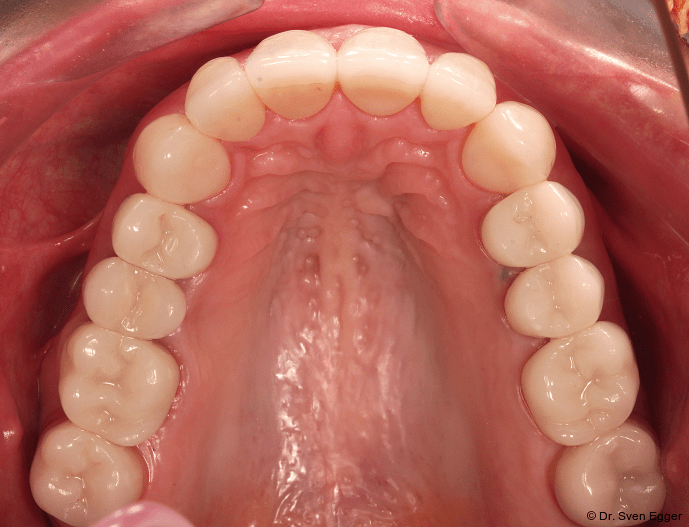

Zusammenfassung der ästhetischen Problematik: Es zeigt sich nun hinsichtlich der Länge (Lächeln), Form, Farbe, Stellung der Zähne sowie der rosa Ästhetik ein ansprechendes dentogingivales Erscheinungsbild. Die unteren Frontzähne haben leichten Kontakt auf den Palatinalflächen der oberen Eck- und Schneidezähne. Der Overbite beträgt 4 mm. Der Overjet 2 mm (Abb. 16+17).

Nachuntersuchung (15-Jahres-Follow-up)

Die Follow-up-Untersuchung zeigte ein Ergebnis, mit dem die Patientin nach 15 Jahren Tragezeit weiterhin vollumfänglich zufrieden ist. Die keramische Teilkrone an Zahn 17 wurde am 31.5.2022 aufgrund Debondings nach erneuter Konditionierung wieder eingesetzt. Die Kieferhöhlen sind verschattungsfrei und zeigen keine Anzeichen eines Rezidivs der in 2007 erfolgten Zystenoperation in der rechten Kieferhöhle (Mukozele). Die endodontisch revidierten Zähne 25 und 45 zeigen weder klinisch noch röntgenologisch Auffälligkeiten. Die Stellung der Ober- und Unterkieferfront sowie die in ZKP etablierte horizontale und vertikale Relation des Unterkiefers ist stabil und bereitet keinerlei Schwierigkeiten. Die Implantate weisen klinisch und röntgenologisch schöne Hart- und Weichgewebsverhältnisse auf. Die häusliche Mundhygiene ist sehr gut. Es sind keine Anzeichen einer Funktionsproblematik zu erkennen. Die Michigan-Schiene wurde 2022 erneuert. Für die vorliegende Situation lässt sich damit auch weiterhin eine sehr gute Langzeitprognose aussprechen (Abb. 18–25).